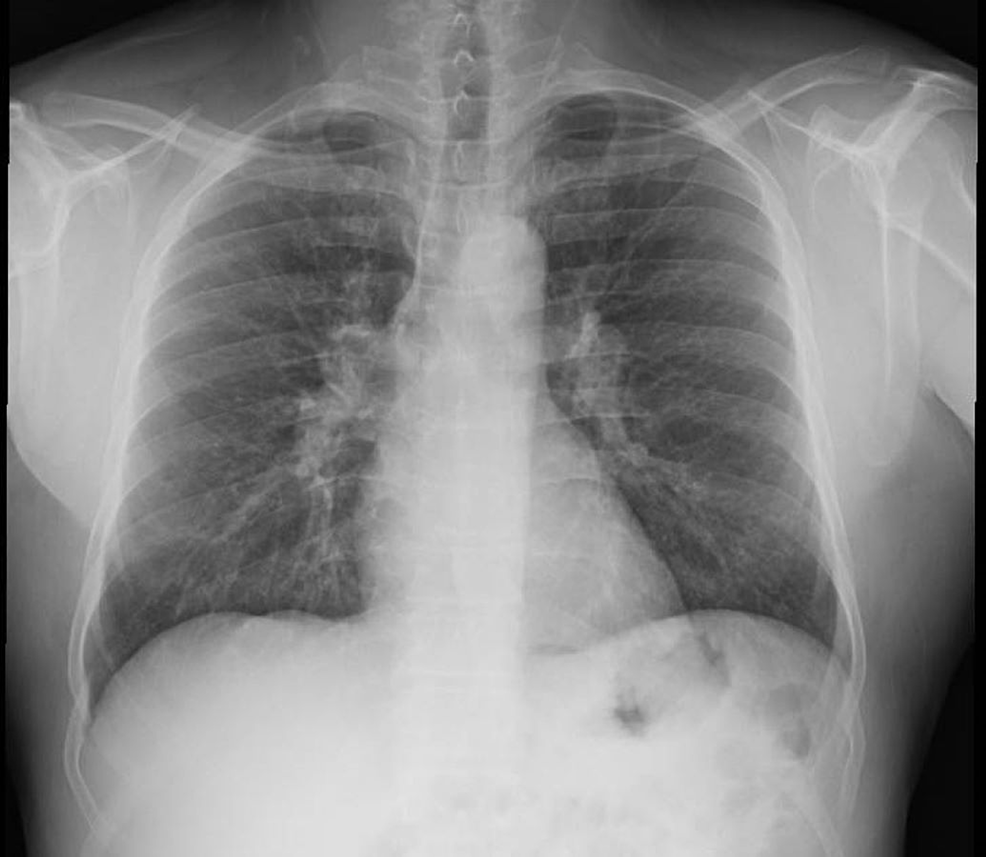

Chest X Ray Eosinophilic Pneumonia . The integration of clinical, radiologic, and. Characteristic imaging findings are often detected with chest radiography, and ct best shows parenchymal abnormalities. Diagnosis of eosinophilic pulmonary diseases. Response to therapy may be assessed based on the following parameters: Eosinophilic lung diseases are a heterogeneous group of disorders that are characterized by excess infiltration of. Eosinophilic pneumonia represents a heterogeneous group of lung disorders characterized by the presence of peripheral blood eosinophilia (defined as an.

Response to therapy may be assessed based on the following parameters: Characteristic imaging findings are often detected with chest radiography, and ct best shows parenchymal abnormalities. The integration of clinical, radiologic, and. Diagnosis of eosinophilic pulmonary diseases. Eosinophilic lung diseases are a heterogeneous group of disorders that are characterized by excess infiltration of. Eosinophilic pneumonia represents a heterogeneous group of lung disorders characterized by the presence of peripheral blood eosinophilia (defined as an.